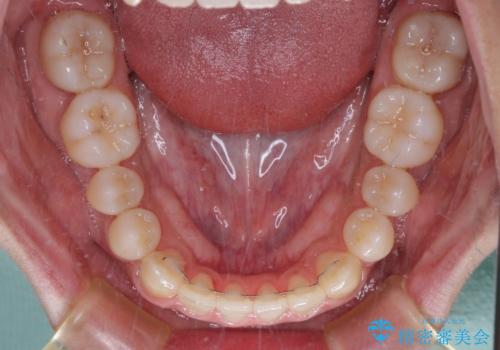

- 前歯のクロスバイトを気にして来院された患者様です。

1年半後に結婚式が控えているとのことで、ワイヤー矯正で早めに治療を終えることを希望されました。

骨格的に下顎が前方に位置していましたが、歯列矯正で改善できると判断し、ワイヤー装置にて矯正治療を行うこととしました。